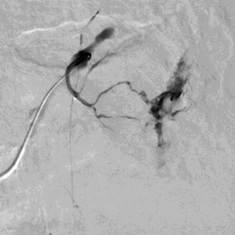

腹腔动脉造影也未发现出血 |

第二天病人持续出血,发现胰横动脉分支供血的部位出血(在PTCD管的左侧) |